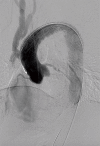

Figure 2

Completion angiography confirming adequate position of the graft and sealing of the PAU. PAU, penetrating atherosclerotic ulcer.